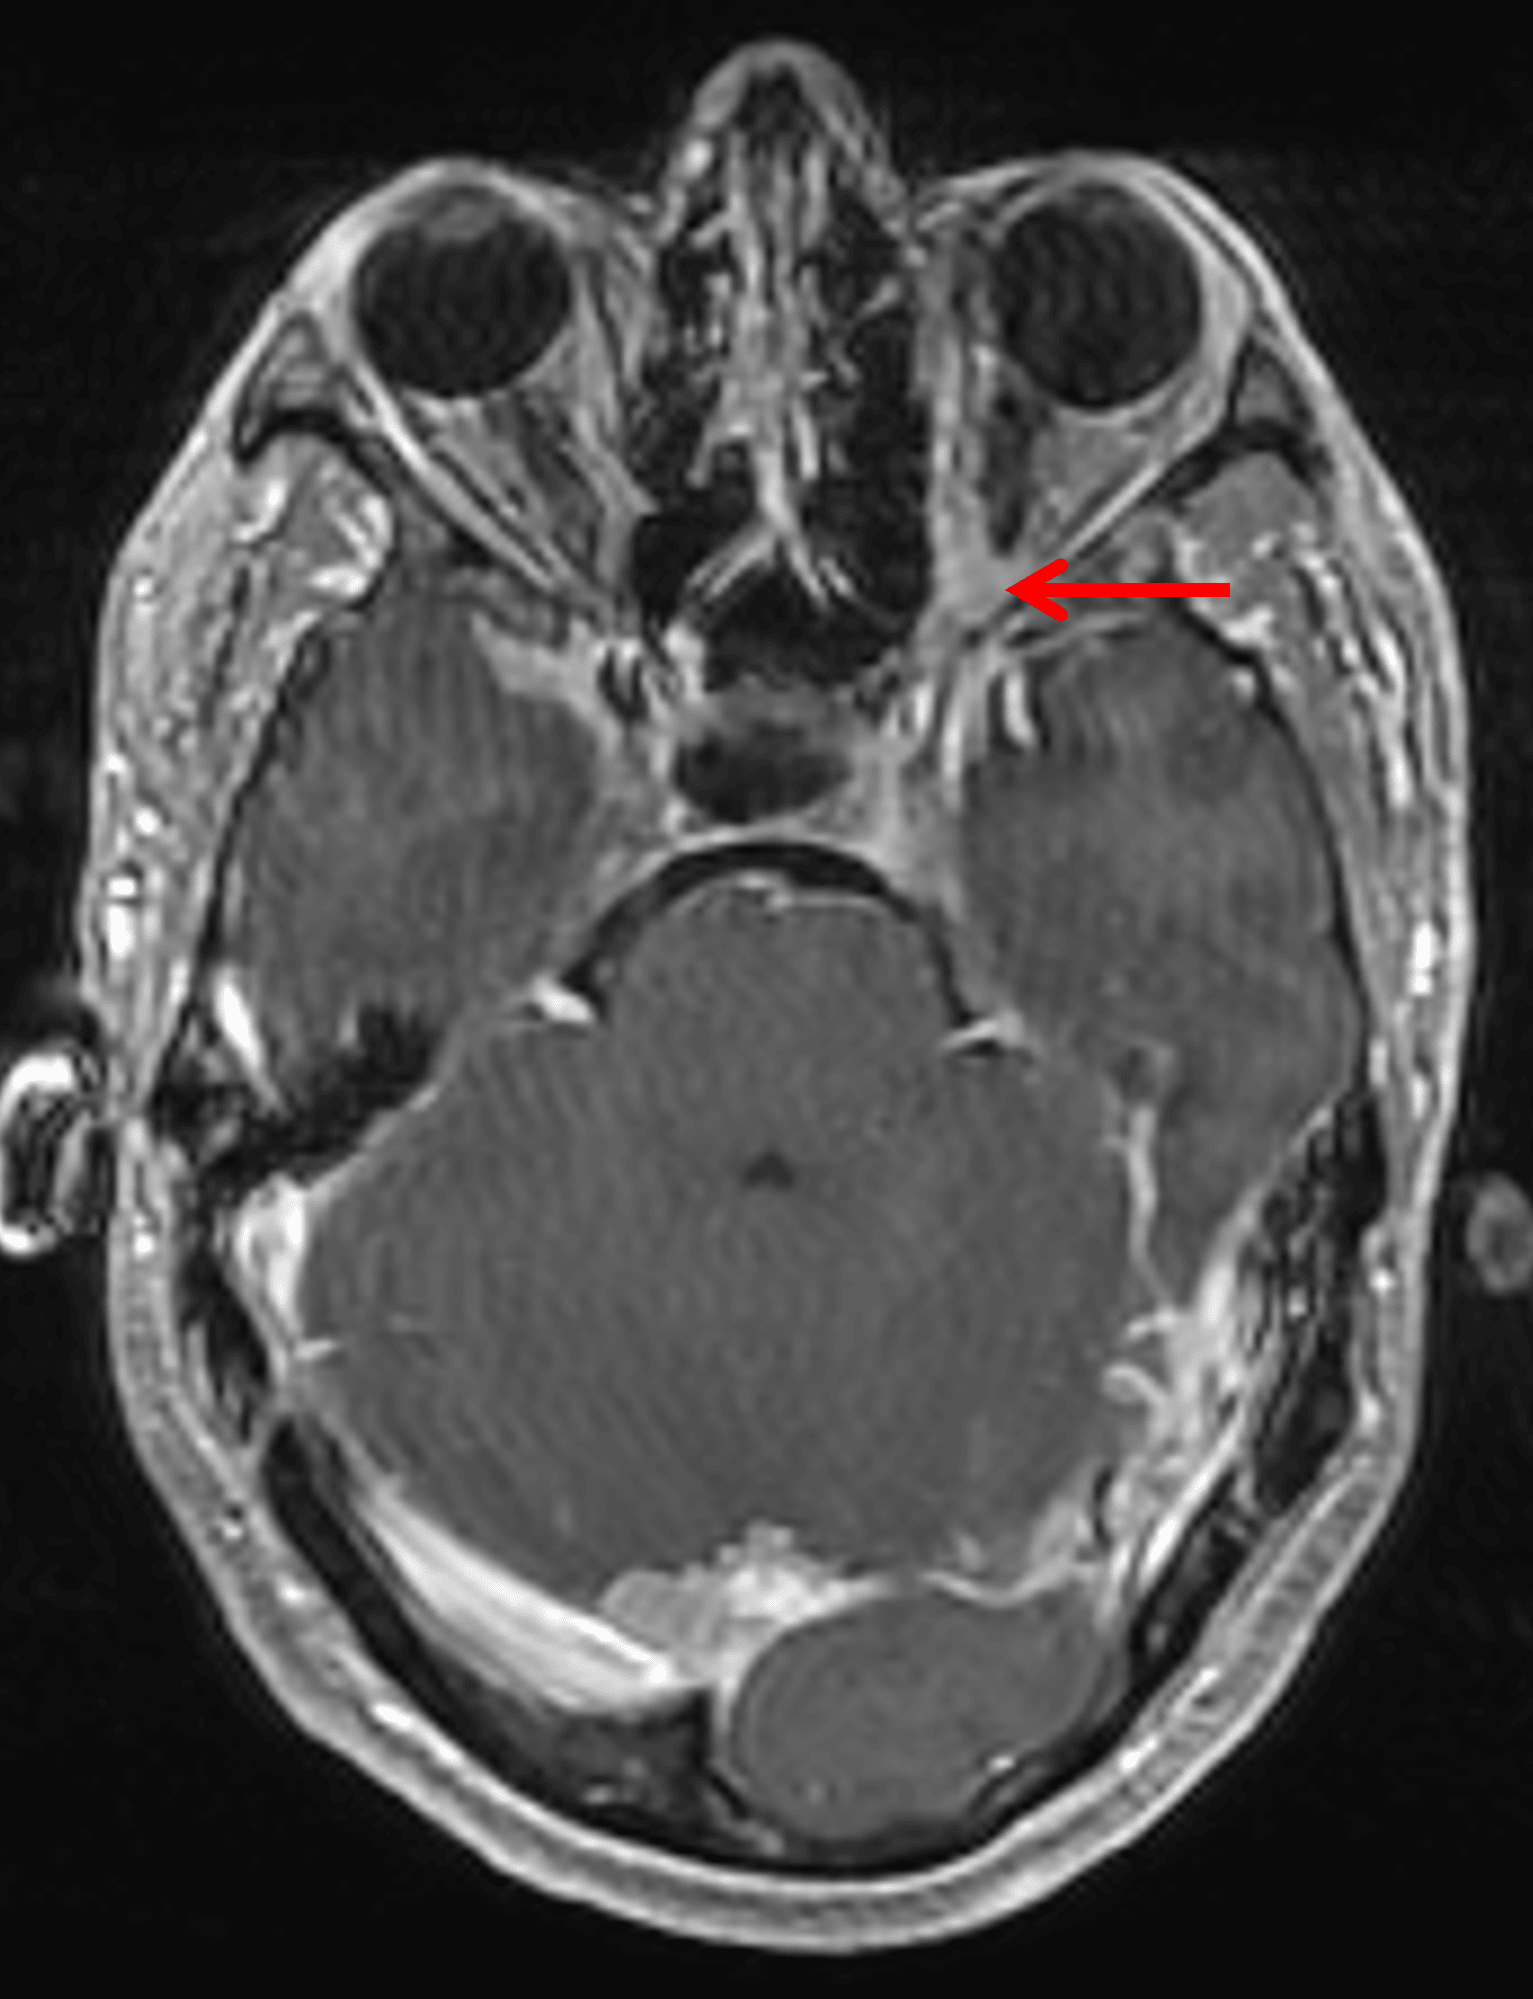

Enhancement in the left orbital apex along the optic nerve (red arrow), likely representing an optic nerve sheath meningioma.

• Amorphous enhancing lesion along the posterior intraorbital left optic nerve near the orbital apex